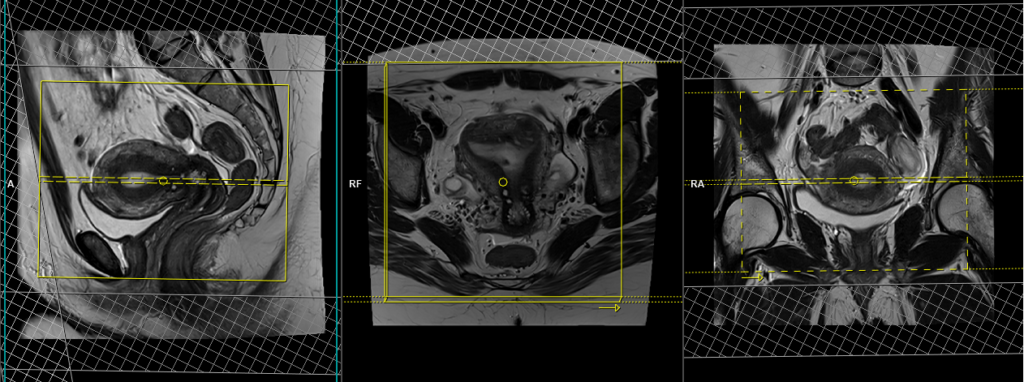

T2 tse sagittal 3mm SFOV

Plan the sagittal slices on the axial plane and angle the positioning block parallel to the line along the linea alba and median sacral crest. Verify the positioning block in the other two planes. In the coronal plane, an appropriate angle must be given, which should be parallel to the lumbosacral spine. Make sure that the slices cover the entire pelvis from the right acetabulum to the left acetabulum. The field of view (FOV) should be sufficiently large to encompass the entire pelvis, typically ranging from 270mm to 300mm. To minimize artifacts caused by arterial pulsation, peristalsis, and breathing, consider adding saturation bands on top and in front of the sagittal block. Ensure an adequate level of phase oversampling to prevent any wrap-around artifacts.

Due to the increased signal-to-noise ratio (SNR) in new generation scanners, motion artifacts can be significant when acquiring images in the anterior-posterior phase direction. This is primarily attributed to the movement of abdominal fat, which exhibits higher signal intensity and can cause ghosting effects over the sagittal images. Therefore, to mitigate this issue, scans are typically performed using a head-to-feet phase direction.

Parameters

TR 3000-4000 | TE 100-120 | SLICE 3 MM | FLIP 130-150 | PHASE A>P | MATRIX 320X320 | FOV 270-300 | GAP 10% | NEX(AVRAGE) 4 |